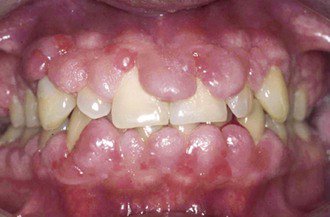

Efectes secundaris de la ciclosporina

La Ciclosporina utilitzada com a tractament inmunosupresor (↓ IL-2), pot provocar Hiperplàsia Gingival.